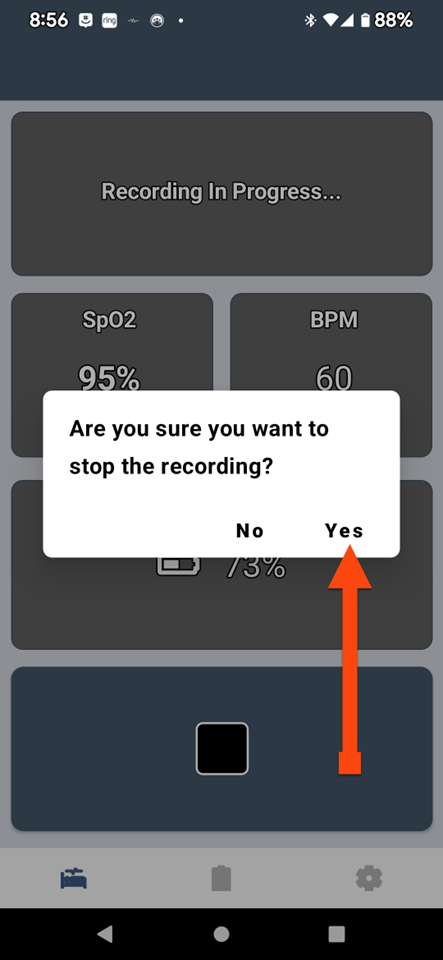

SLEEPIMAGE APP (Android)

SLEEPIMAGE APP (Android)

SLEEPIMAGE APP (Android)

SLEEPIMAGE APP (Android)

SLEEPIMAGE APP (Android)

SLEEPIMAGE APP (Android)

SLEEPIMAGE APP (Android)

SLEEPIMAGE APP (Android)

SLEEPIMAGE APP (Android)

SLEEPIMAGE APP (Android)

SLEEPIMAGE APP (Android)

SLEEPIMAGE APP (Android)

SLEEPIMAGE APP (Android)

SLEEPIMAGE APP (Android)

SLEEPIMAGE APP (Android)

SLEEPIMAGE APP (Android)

SLEEPIMAGE APP (Android)

SLEEPIMAGE APP (Android)

SLEEPIMAGE APP (iPhone)

SLEEPIMAGE APP (Android)

SLEEPIMAGE APP (Android)

SLEEPIMAGE APP (Android)

SLEEPIMAGE APP (Android)

SLEEPIMAGE APP (Android)

SLEEPIMAGE APP (Android)

SLEEPIMAGE APP (Android)

SLEEPIMAGE APP (Android)